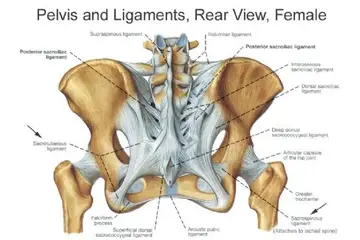

- Görüntüleme yöntemleri: Röntgen, MRI (Manyetik Rezonans Görüntüleme) ve CT (Bilgisayarlı Tomografi) gibi yöntemler, kemik yapısını değerlendirmek için kullanılır.

- Cerrahi müdahale: Gerekli durumlarda, kemik onarımları veya eklem değişimi gibi cerrahi işlemler düşünülebilir.